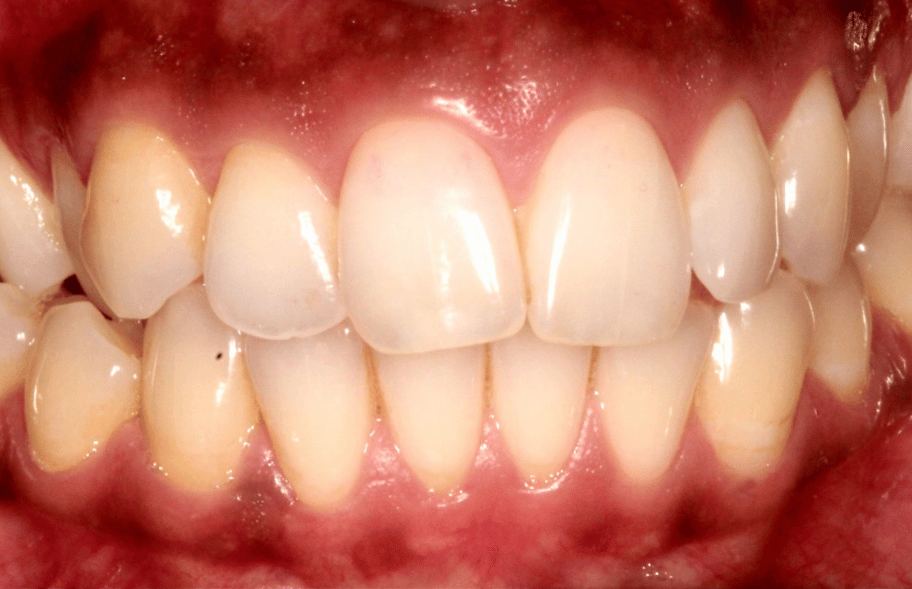

Before

Before